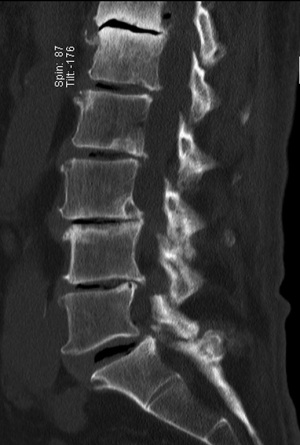

A 62-year-old female presented with a 3-week history of severe left lower thoracic radicular pain. The patient had no neurological deficit on examination. She had no medical comorbidities and was a non-smoker. Initial chest CT and ultrasound were unremarkable. MRI thoracolumbar scan showed an acute, moderate sized, left sided T9-10 foraminal soft disc prolapse extending superiorly into the left T9-10 foramen with significant compression of the exiting left T9 nerve root (Figure 4). The patient was unresponsive to opiate analgesia, pregabalin (Lyrica®, Pfizer, New York, NY, USA) and CT guided left T9 transforaminal epidural nerve root injection. The patient underwent a left sided transpleural T9-10 LIF. Following formal discectomy, a ball tipped blunt hook was inserted superiorly into the T9-10 foramen for removal of extruded disc fragments. A standalone interbody cage (6×16×40 mm3, zero degree, CoRoent XL-T) was placed. EBL was less than 50 mL. A chest tube was not required. Postoperative chest radiography excluded pneumothorax. CT showed satisfactory prosthesis placement at T9-10 with no residual neural compression (Figure 5). The patient reported reduction in preoperative thoracic pain (VAS 9/10 to 5/10), further improved to 2-3/10 with a CT guided T9-10 epidural injection. She was discharged to home 5 days after surgery. At 3 months postoperative, the patient continued to exhibit mild persistent neuropathic thoracic pain requiring paracetamol and pregabalin 75 mg daily, but had returned to part-time work duties. At 6-month follow-up she had solid interbody fusion, confirmed on CT, and had resumed full-time work. At 24 months follow-up the patent reported further improvement in pain (VAS 1-2/10); her ODI (56 to 24), PCS (33 to 48) and MCS (44 to 62) were also improved.